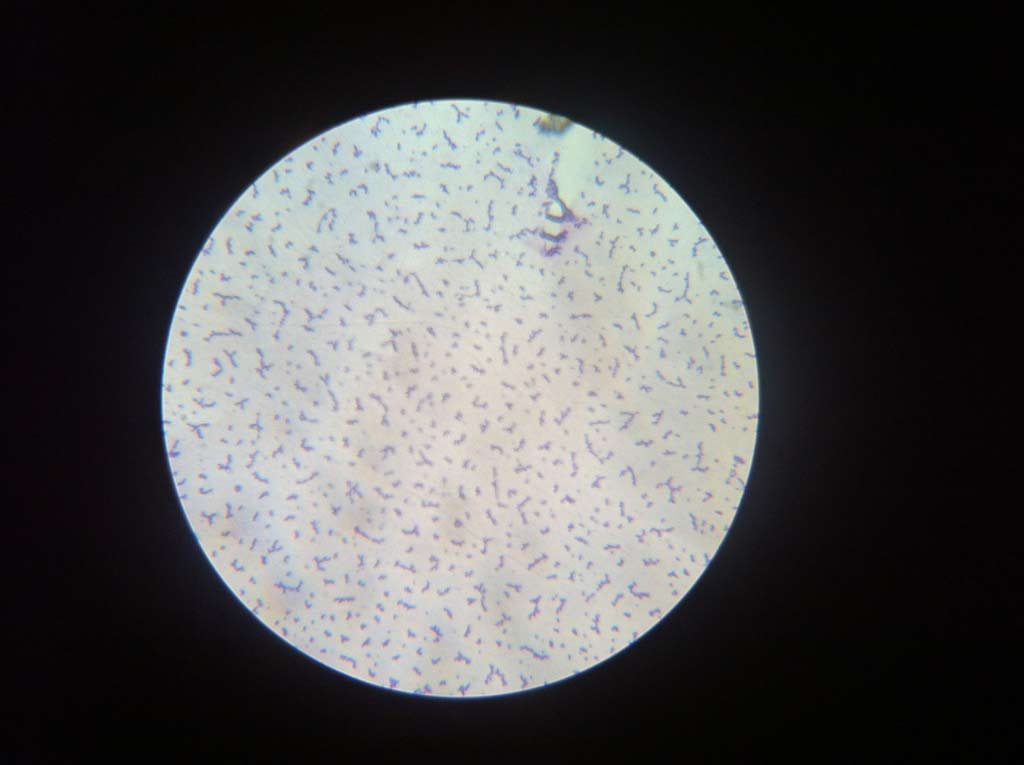

Microscopisch beeld van het gewrichtsvocht van een veulen. Bij dit veulen zijn er grote hoeveelheden ettercellen aanwezig. Dit wijst op een slechte afweer van het lichaam van het veulen waardoor bacteriën zich kunnen nestelen en vermenigvuldigen.